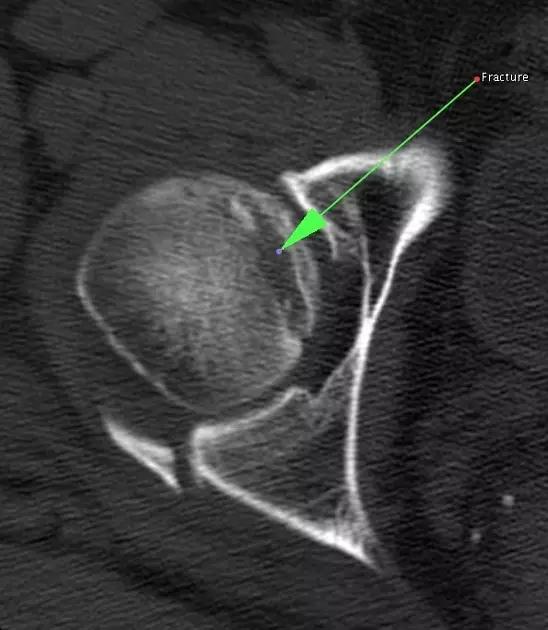

Hill-Sachs 损伤的 CT 片 (来源:Hill-Sachs Injuries of the Shoulder)